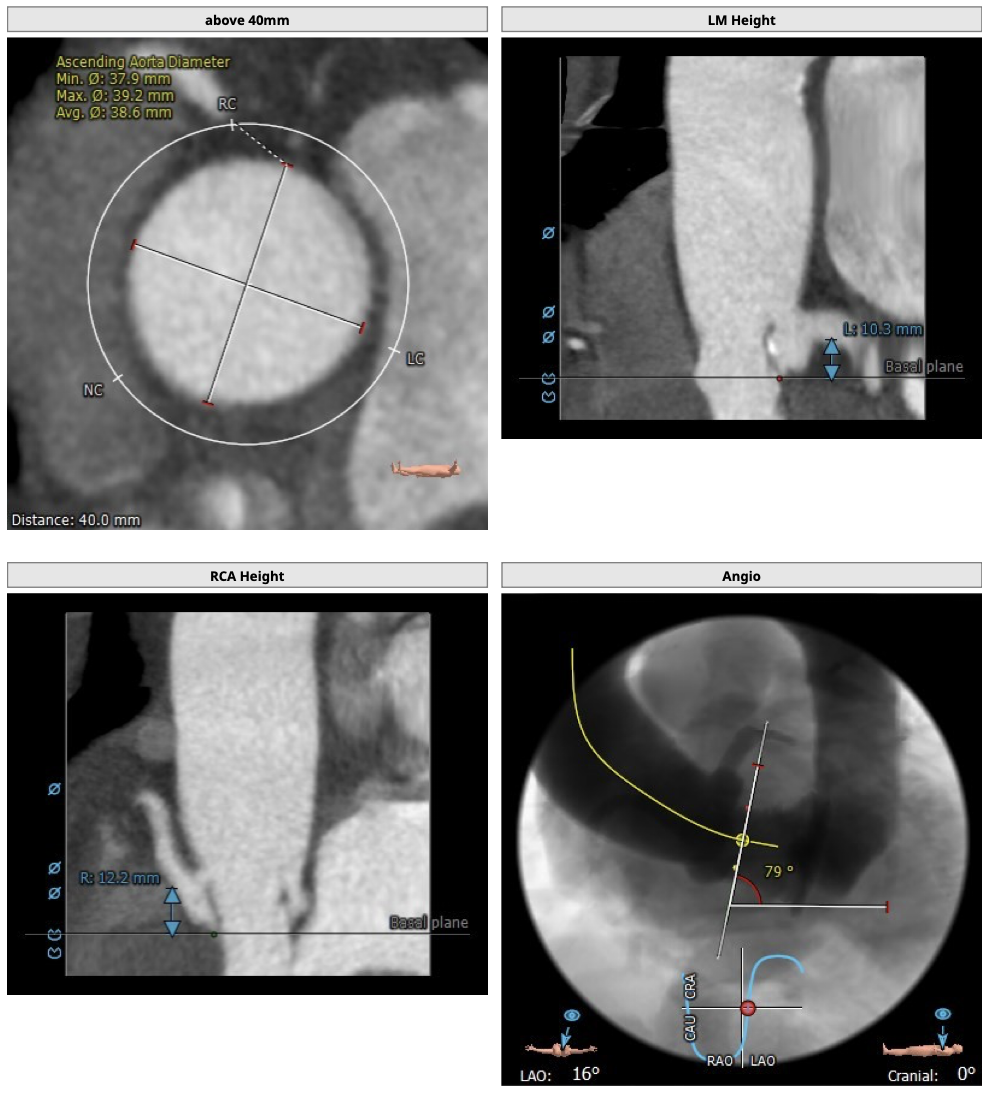

主动脉CT

难点分析:

*患者为四叶瓣,单纯返流,瓣膜锚定具有有一定难度,对释放瓣膜的把控要求高;

*右冠高度可,但左冠高度稍低,具有一定冠脉风险;

*心脏角度略大,释放瓣膜时,瓣膜与瓣环同轴性差。

制定策略:

经分析研判,拟从右侧股动脉穿刺入路,结合患者返流特点与主动脉根部结构,选用L26号的VenusA-Valve瓣膜,使用VenusA-Plus可回收输送系统,确保手术安全和瓣膜的稳定释放,必要时可使用圈套器辅助瓣膜释放,瓣膜释放后结合造影和超声情况,决定是否后扩。